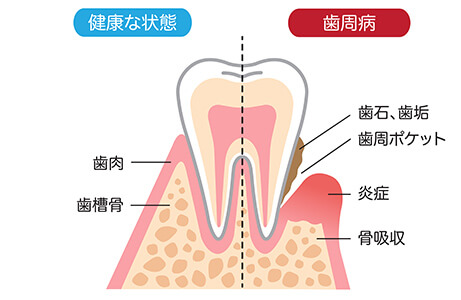

歯周病は、歯垢(プラーク)という細菌の塊が歯と歯ぐきの間の歯周ポケットに溜まり、細菌が繁殖することによって引き起こされます。歯垢は放置すると石灰化して歯石となり、日々の歯みがきでは除去できなくなる上、歯周ポケットを深くする原因となり、歯周病を進行させてしまいます。

炎症が続いていると歯周病菌や菌から発せられる毒素が血中から心臓や肺に運ばれ、全身疾患に繋がる恐れがございます。